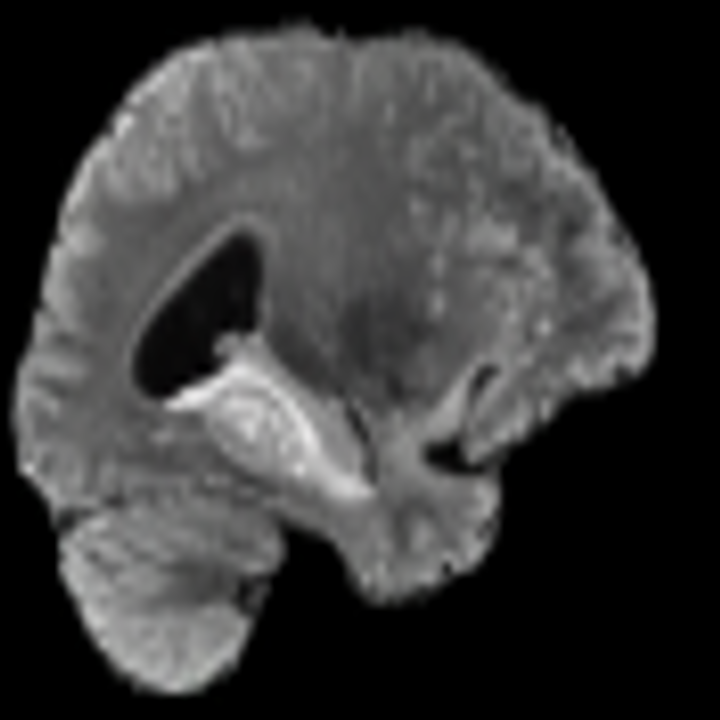

One way to test the generalization capability of the trained X-Diffusion is to test it on a completely different domain from an MRI dataset not seen during training. We report the single-slice results on the test set of knees from NYU fastMRI [33, 80], using the X-Diffusion trained on the BRATS brain MRIs. The test PSNR result is 34.17 and an example is shown in Figure 8. It shows how successfully X-Diffusion can generate knee MRIs (out-of-domain) despite being trained on brains.

The Effect of Pretraining. We hypothesize that the massive pretraining of our X-Diffusion based on Stable Diffusion weights [55] played an important role. Another aspect is that the Zero-123 [39] weights which are modified Stable Diffusion weights that understand viewpoints and fine-tuned on large 3D CAD dataset Objaverse [21] can indeed be the reason why X-Diffusion generalizes well. The PSNR for 1-slice on BRATS dataset are (SD-pretraining): 21.52 dB, (Zero-123-pretraining): 23.13 dB, (no-pretraining): 17.14 dB. These results highlight the importance of pertaining to X-Diffusion. Refer to Figure 8 for similar observation.

The Effect of Pretraining. We hypothesize that the massive pretraining of our X-Diffusion based on Stable Diffusion weights [55] played an important role. Another aspect is that the Zero-123 [39] weights which are modified Stable Diffusion weights that understand viewpoints and fine-tuned on large 3D CAD dataset Objaverse [21] can indeed be the reason why X-Diffusion generalizes well to out-of-domain dataset (see generalization to knee MRIs in Figure 19).